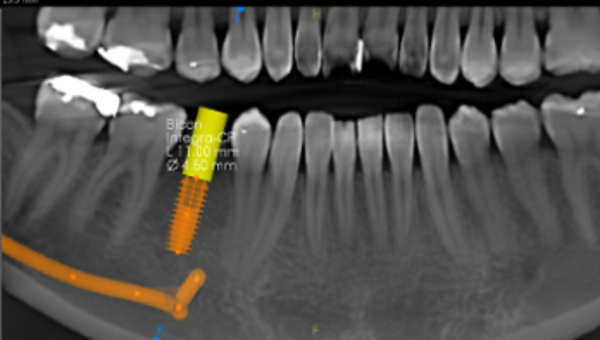

Implant planning

• Implant site measurements: first 3 implants FREE, then + $30/each